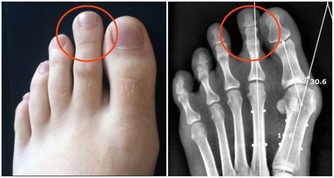

膝關節構造是由骨頭,即股骨、脛骨、髕骨,關節軟骨及軟組織,如關節滑囊、關節液及周圍肌肉韌帶構成,關節軟骨是否正常,以及關節液是否充足,都仰賴關節負重活動,如走、跑、跳等,幫助關節靈活順暢。

然而,久坐不但沒有讓關節承重,膝關節通常彎曲超過90度,此時膝關節壓力上升,生物力學的改變造成周邊韌帶張力過大,久而久之即可能發炎情況;此外,久坐不動易導致大腿肌力弱化,不足以穩定膝關節,更加速膝關節退化。

由於藥物及復健皆難以直接改善軟組織及關節面軟骨問題,因此增生療法近年來成為治療的一環,主要在於鎖定軟組織病灶及關節面軟骨來施打藥劑,如高濃度葡萄糖、維生素B12、自體血小板生長因子等,幫助軟骨修復及軟組織回復強韌,以提升生理結構完整性與關節穩定度。